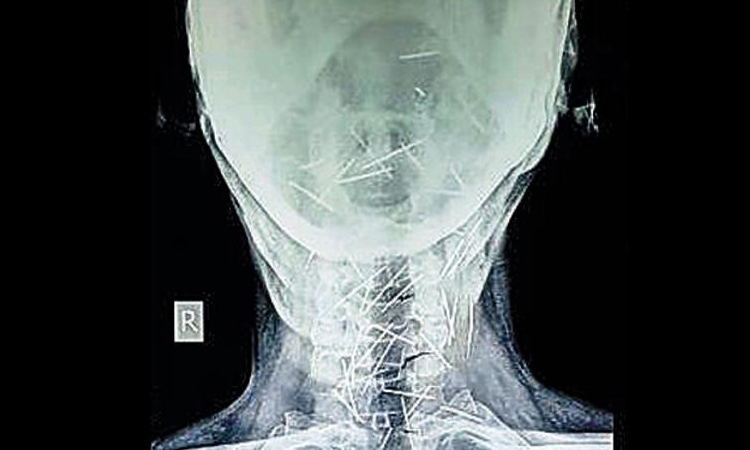

ശരീരത്തിൽ 75 പിന്നുകളുമായി ഒരു മനുഷ്യൻ

text_fieldsജയ്പൂർ: പിന്നുകൊണ്ട് നിർമിച്ച മനുഷ്യ കുഷ്യൻ എന്നു വിളിക്കാം രാജസ്ഥാൻ സ്വദേശി ബദ്രിലാൽ മീണയെ. 75 പിന്നുകളാണ് 56കാരനായ ബദ്രിലാലിെൻറ ശരീരത്തിൽ നിന്ന് കണ്ടെത്തിയത്. കഴുത്ത്, കൈത്തണ്ട, കാലുകൾ എന്നീ ഭാഗങ്ങളിൽ തൊലിക്കടിയിലായാണ് പിന്നുകൾ കാണപ്പെട്ടത്.

ഒരിഞ്ചോളം നീളമുള്ള പിന്നുകൾ ശരീരത്തിലെത്തിയതെങ്ങനെ എന്ന് വ്യക്തമാകാതെ കുഴങ്ങിയിരിക്കുകയാണ് ഡോക്ടർമാർ. പിന്നുകൾ കുത്തിക്കയറ്റിയ അടയാളങ്ങളൊന്നും ശരീരത്തിലില്ല. വിഴുങ്ങിയതല്ലെന്ന് ഡോക്ടർമാർ ഉറപ്പിച്ചു പറയുന്നു.

വയറിലോ, ആമാശയത്തിലോ, െചറുകുടലിലോ പിന്നുകൾ കണ്ടെത്താത്തതിനാൽ വിഴുങ്ങിയതല്ലെന്ന് ഉറപ്പിക്കാമെന്നാണ് ഡോക്ടർമാരുടെ പക്ഷം.

റെയിൽവേ ജീവനക്കാരനായ ബദ്രിലാലിനുമറിയില്ല എങ്ങനെയാണ് പിന്നുകൾ ശരീരത്തിലെത്തിയതെന്ന്.

വലതുകാലിലെ വേദനക്കും പ്രമേഹത്തിനും ചികിത്സക്കായി കോട്ടയിലെ സ്വകാര്യ ആശുപത്രിയിൽ സ്കാനിങ്ങ് നടത്തിയപ്പോഴാണ് സംഭവം ശ്രദ്ധയിൽ പെട്ടത്.